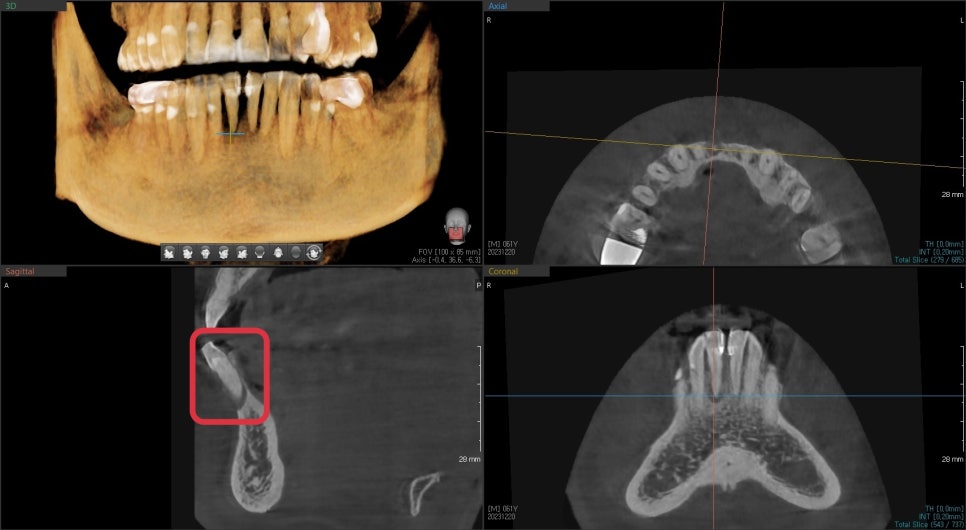

수술 시작 전에 미리 구강 스캐너를 통해

임시치아 제작을 의뢰합니다.

기공소와 임플란트 방향과 예상 치아 형태를 의뢰하여

제작된 임시치아를 임시 기둥을 이용하여 수정합니다.

수술은 치주염이 심해 치조골이 많이 흡수된 곳은

치조골 이식술을 통해 잇몸 볼륨을 유지시켜

시간이 지나도 잇몸이 꺼지지 않도록 유지시켜주고

임시 기둥을 통해 임시치아를 제작했습니다.